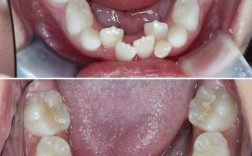

- 替牙期障碍:乳牙早失导致邻牙倾斜占据空间,使恒牙萌出间隙不足;乳牙滞留或多生牙、埋伏牙等,会阻碍正常恒牙排列,引发“虎牙”或牙齿扭转。

下牙齿不齐是口腔常见的错颌畸形之一,表现为牙齿排列拥挤、错位、扭转、稀疏或高低不齐等情况,不仅影响面部美观,还可能对咀嚼功能、发音及口腔健康造成潜在威胁,据统计,我国约70%以上存在不同程度的牙齿排列问题,其中下牙列不齐占比超过40%,且近年来青少年群体的发病率呈上升趋势,需引起重视。